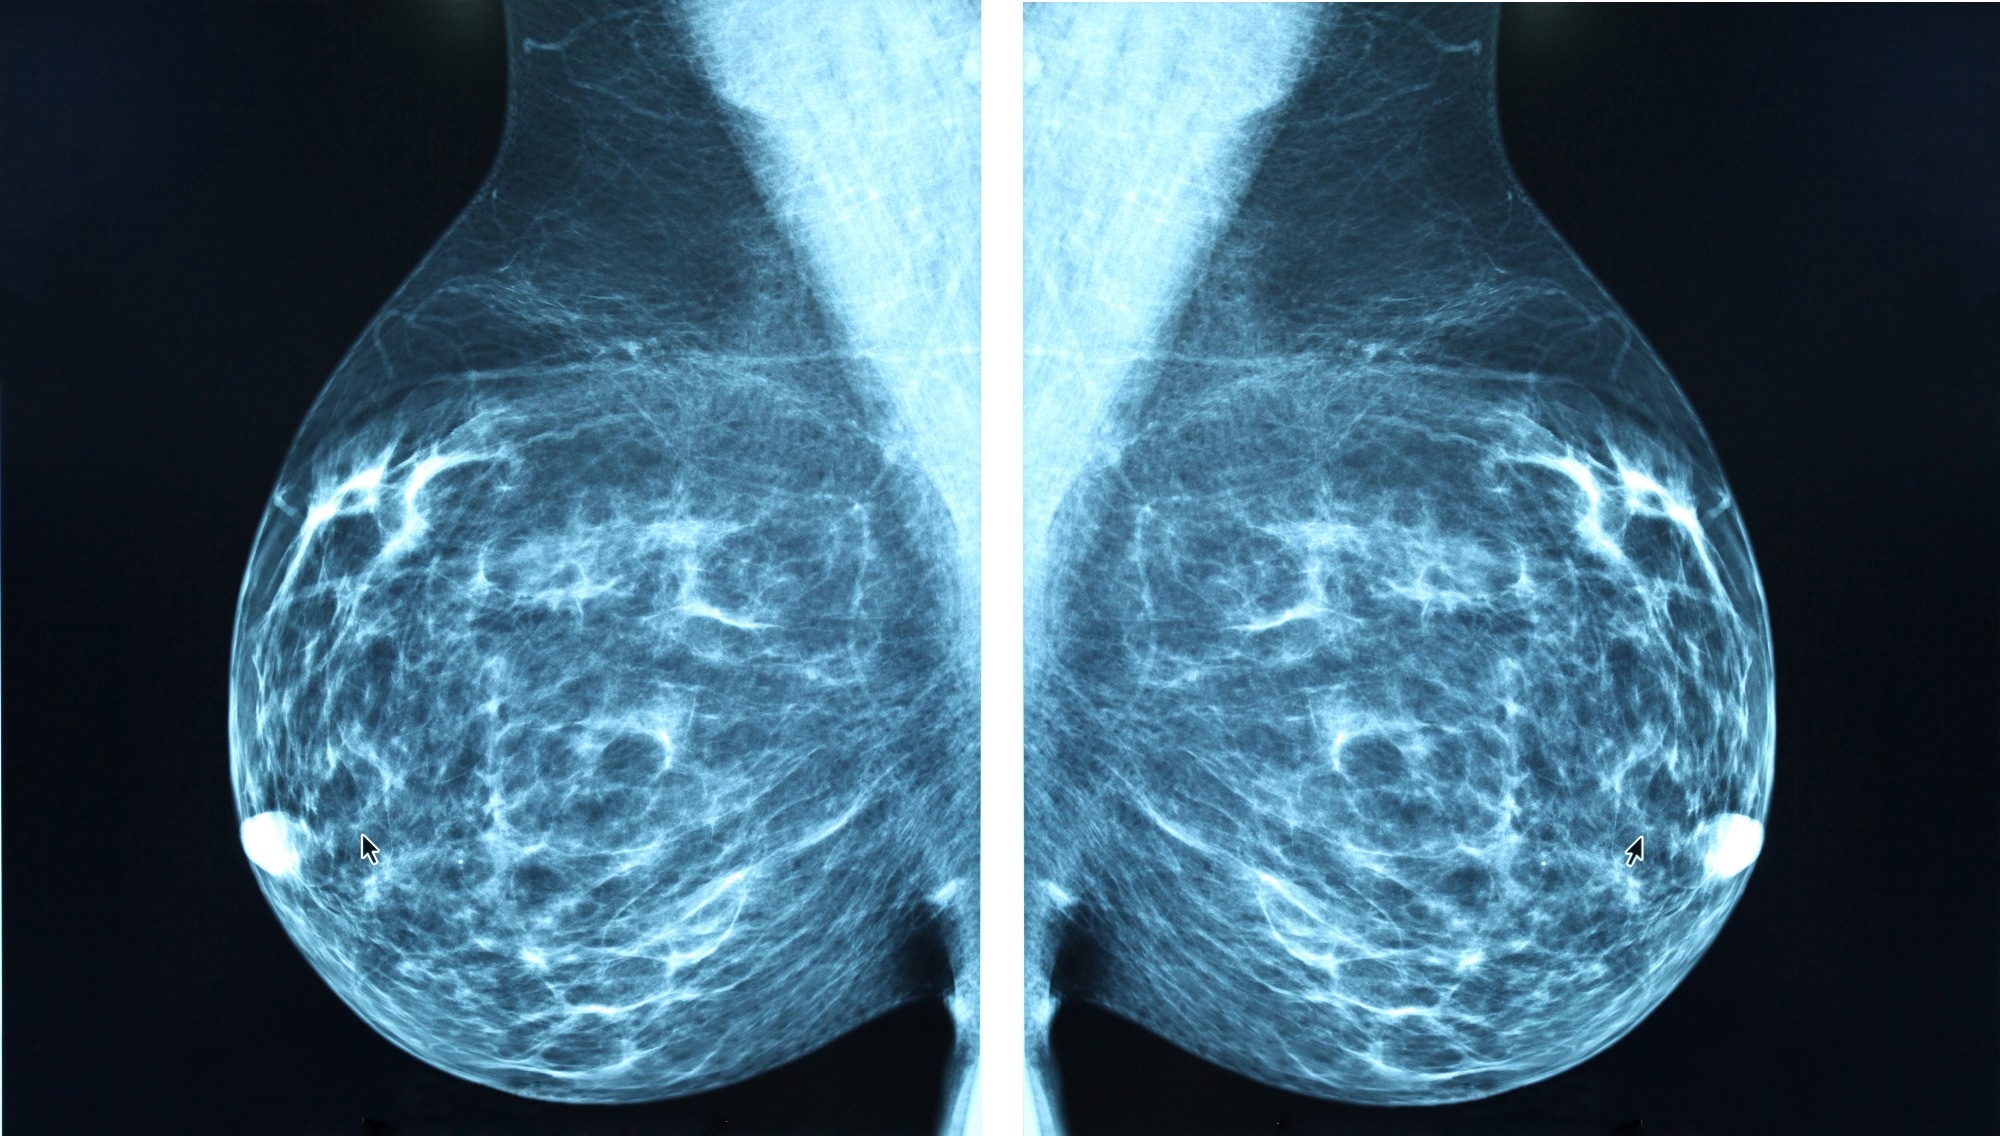

Study: Artificial Intelligence Algorithm for Subclinical Breast Cancer Detection. Image Credit: Blue Planet Earth / ShutterstockStudy: Artificial Intelligence Algorithm for Subclinical Breast Cancer Detection. Image Credit: Blue Planet Earth / Shutterstock

In a recent study published in the JAMA Network Open, researchers evaluated whether a commercial artificial intelligence (AI) tool, originally developed for breast cancer detection, could leverage screening mammograms to estimate the risk of future breast cancer development years before clinical diagnosis. They used a cohort study comprising almost 350,000 screening examinations from 116,495 women to generate AI-based cancer detection scores, which were assessed as proxies for subsequent breast cancer risk rather than for direct diagnosis.

Study findings revealed that the AI algorithm assigned higher cancer detection scores to breasts that would later develop breast cancer, even 4–6 years before clinical diagnosis, compared to breasts that did not develop cancer. This suggests that commercial AI tools may help identify women at higher risk of developing breast cancer well in advance of diagnosis, providing a pathway for more personalized risk-based screening and earlier intervention.